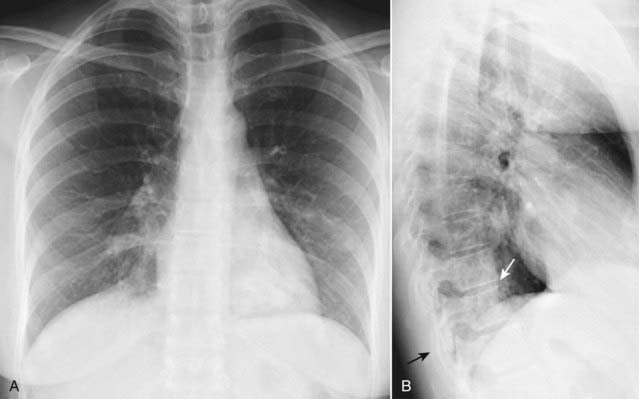

Figure 2-7 Fluid in the major fissures.

Left lateral view of the chest shows thickening of both the right and left major fissures (solid white arrows). This patient was in congestive heart failure and this thickening represents fluid in the fissures. Normally, the fissures are either invisible or, if visible, they are fine, white lines of uniform thickness no larger than a line made with the point of a sharpened pencil. The major or oblique fissure runs from the level of the 5th thoracic vertebral body to a point on the anterior diaphragm about 2 cm behind the sternum. Notice the increased interstitial markings that are visible throughout the lungs and are due to fluid in the interstitium of the lung.